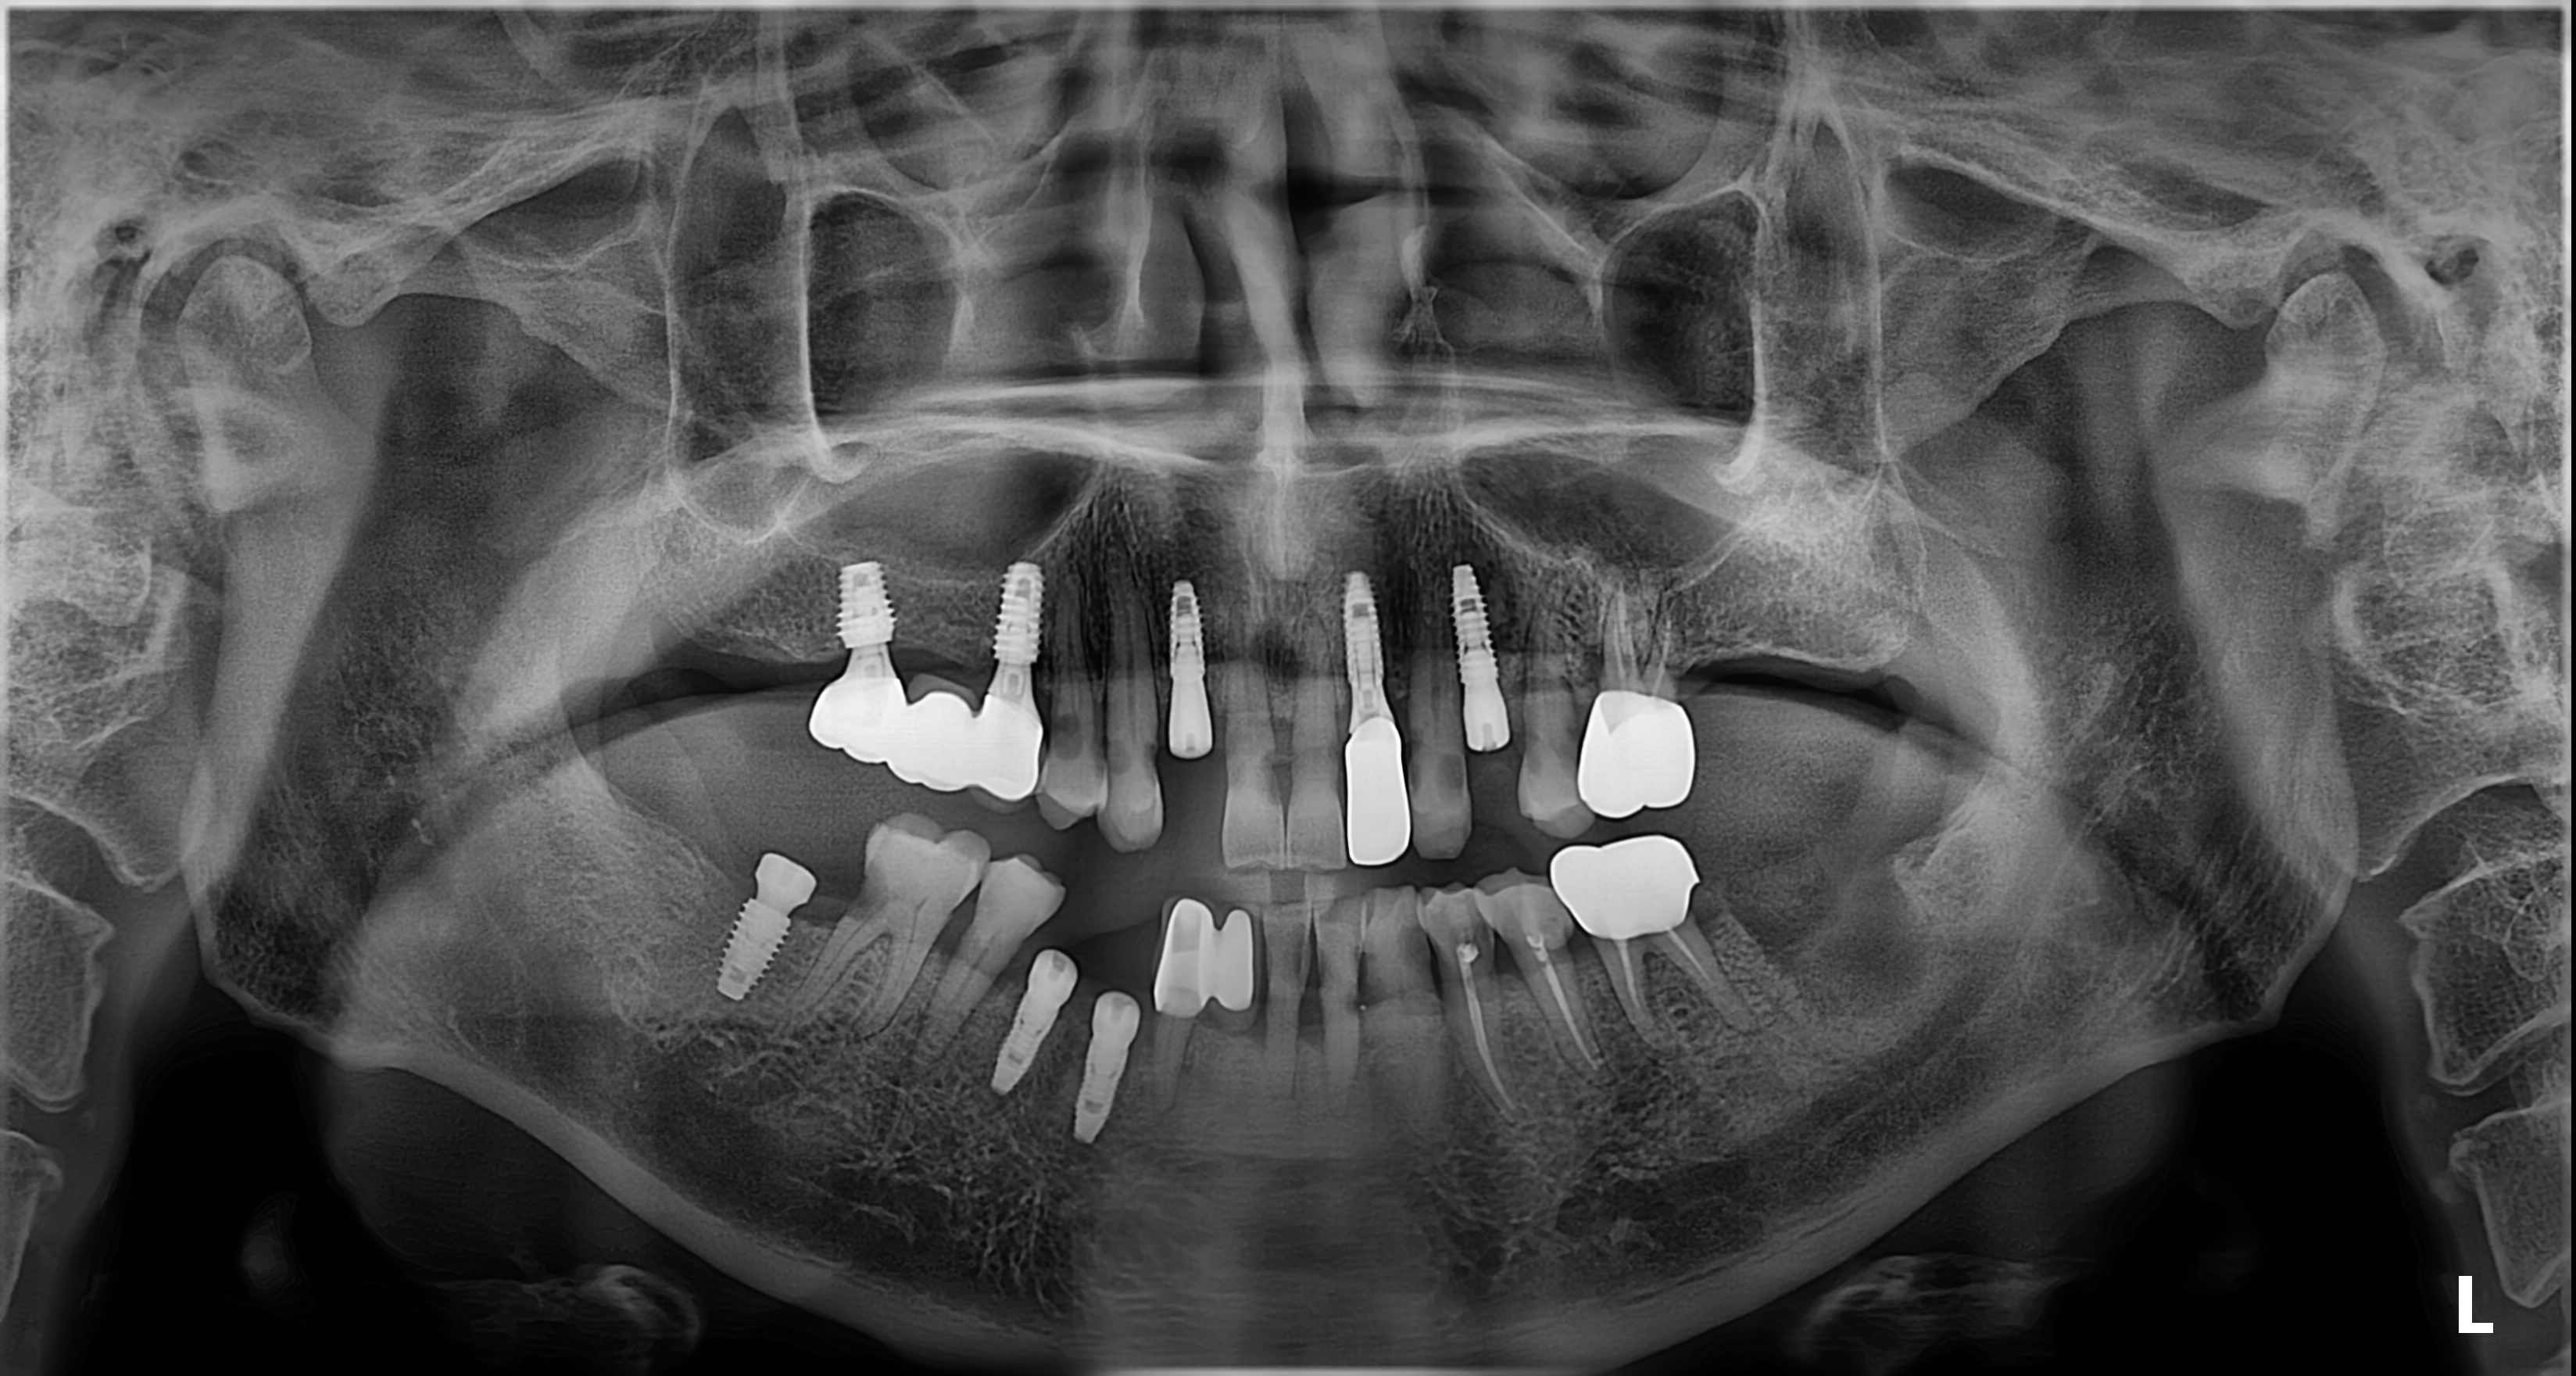

전악 임플란트가

한시간만에?

안면 골격을 다루는

구강악안면외과 전문의 경험으로

짧은 시간에도 정밀한 식립을 완성합니다.

임플란트 시술 사진

임플란트의 5년 성공율은

최근 발표된 논문들까지 종합해도

90~95% 이상으로 발표되고 있습니다.

매우 높은 성공율입니다.

하지만, 실패한 임플란트를 같은 자리에

재식립했을 때의 성공률은 70%대로 떨어집니다.

(J Oral Maxillofac Surg 78:375-385, 2020)

초기에 발견하고 재식립했을 때는 성공율이 높아집니다.